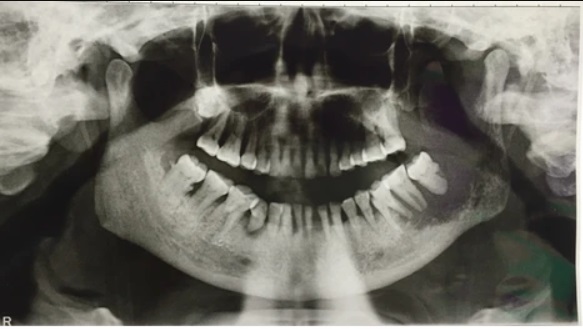

If oral cancer is suspected, a healthcare professional will conduct a thorough examination of the mouth and throat. This may include a physical examination, a biopsy of any suspicious areas, and imaging tests such as X-rays, CT scans, or MRI scans. The biopsy involves removing a small sample of tissue for laboratory analysis, which helps determine if cancer cells are present. Once a diagnosis is confirmed, the cancer is staged to determine the extent of its spread. Staging is important for treatment planning and prognosis.

Our comprehensive evaluation, which includes a teeth assessment and head x-ray, equips our expert dentist Burwood to offer you personalized cosmetic treatment advice tailored to your oral health and facial structure. Aimed at enhancing your smile to its fullest potential, our no-obligation consultation will empower you with in-depth knowledge and recommendations.